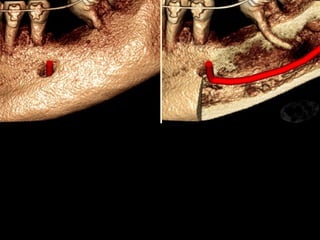

Conducto Dentario Inferior

C.Interna

2,5mm

C. Externa

5,5mm

Basal

Distancia al Apice de los Molares

Según E. Oliver

Lingual Vestibular

5 a 6mm

Dentario Inferior-Basal

Mandibular

Distancia máxima

12 mm

Distancia promedio

8 mm

Distancia mínima

5mm